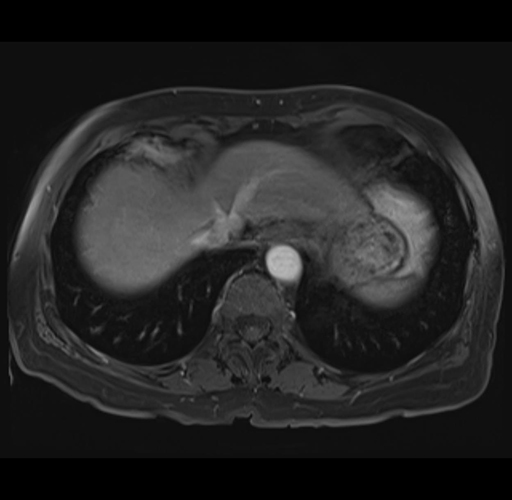

MRI T1